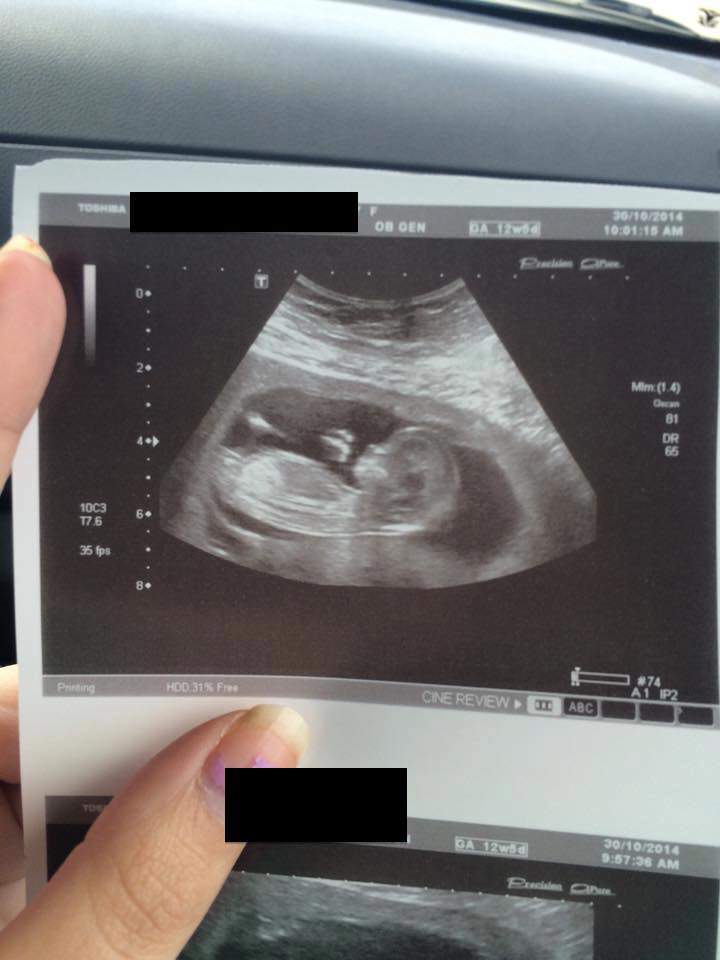

Hi Everyone could you please have a look at my nub pic and let me know what you think :)

Thinking pink :)

pink

am I the only one who sees the little bubble thing at the end of the nub? its laying flat but I can see a little thing! ?

Girl

Looks girly to me, congrats!

Girl.

Girly on 2nd PIC for me X

I would guess girl :)